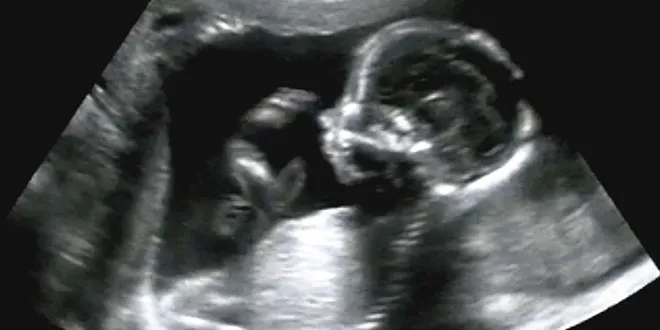

C’est une certitude : les fœtus âgés de 20 semaines souffrent lors d’un avortement

Un spécialiste en néonatalogie l’affirme : les bébés prématurés de 20 semaines sont viables, ils bougent et peuvent souffrir. Ces mêmes bébés in utero souffrent aussi quand ils sont victimes d’un avortement.